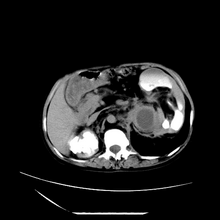

女性,41岁,发现左腹部包块3年,现行ct检查,检查前做过静脉肾盂造影。

左侧低密度区是脂肪密度,中间可见条索状软组织样密度影,现主要想知道左肾前下缘圆形软组织样密度影,内见低密度水样密度影,这是什么?

脾脏增大,左肾后方脂肪增多,脊柱前方脂肪增多,左肾窦脂肪增多,左肾变形,双肾积水以左侧为著,左肾内侧及上方见环形软组织肿物影,内部低密度区,考虑1盆腹腔/腹膜后及左肾窦脂肪增多症2左肾内侧病灶可能为左肾上腺病灶,可能为脂肪增多的原凶

1)考虑左肾替代性脂肪瘤病;不排除左肾错构瘤。2)双肾积水。

肾窦脂肪瘤病及肾替代性脂肪瘤病被认为是脂肪增殖程度不同的一种疾病。正常情况下肾窦内有少量脂肪组织充填,在某种情况下肾实质会发生萎缩,而以肾窦、肾门为中心脂肪或(和)纤维组织可出现增殖,当增殖局限在肾窦、肾门区时称为肾窦脂肪瘤,若同时部分或全部取代了萎缩破坏的肾实质时称为肾替代性脂肪瘤病。

ct典型表现为以肾窦肾门为中心大量弥漫性脂肪积聚,鹿角状结石及萎缩的肾实质。合并肾周感染时,肾轮廓不清,周围有粘连性改变。

诊断rsl的必备条件是肾窦、肾门的脂肪组织增生和肾实质的萎缩,而且本例因为ivp后扫描不好判断有无肾结石但可能性较小;另外,占位效应显著,脾后缘都受压了,肾门以下肾实质残缺,支持肾脏错构瘤.

1、考虑左肾替代性脂肪瘤病,2、双肾积水,3、距脾,4、楼主说的我考虑为感染性病灶。